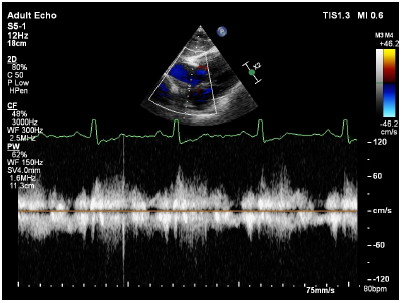

Transthoracic echocardiography showed dilated right atrium, right ventricle with a large atrial septal defect (ASD) with bi-directional shunt and severe pulmonary valve stenosis (Figures 2–4). Bubble's study confirmed the diagnosis of atrial septal defect (Figure 5) Parasternal long-axis view M-mode showed right ventricular hypertrophy of 9mm (Figure 6). Further plan for trans-esophagealechocardiography was discussed with patient but due to financial constraints as a foreigner, he decided to continue investigations in his home country. The patient was rehydrated with intravenous fluid therapy and was discharged with referral letter to home country.

Figure 3 Pulse wave doppler over ASD showing bidirectional shunt.